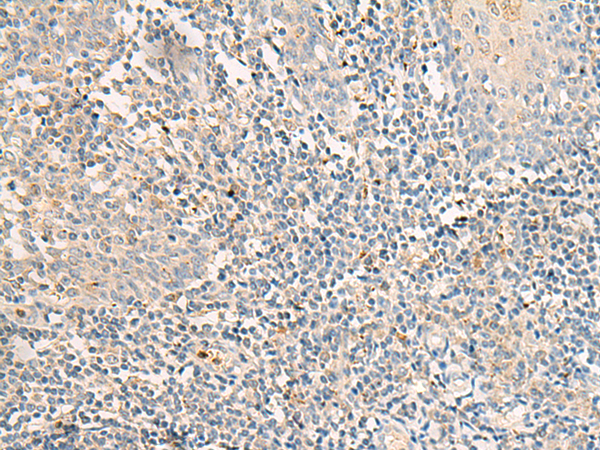

分类: 科研抗体货号: P06608别名: RP78; P114-RhoGEF应用: IHC反应种属: Human